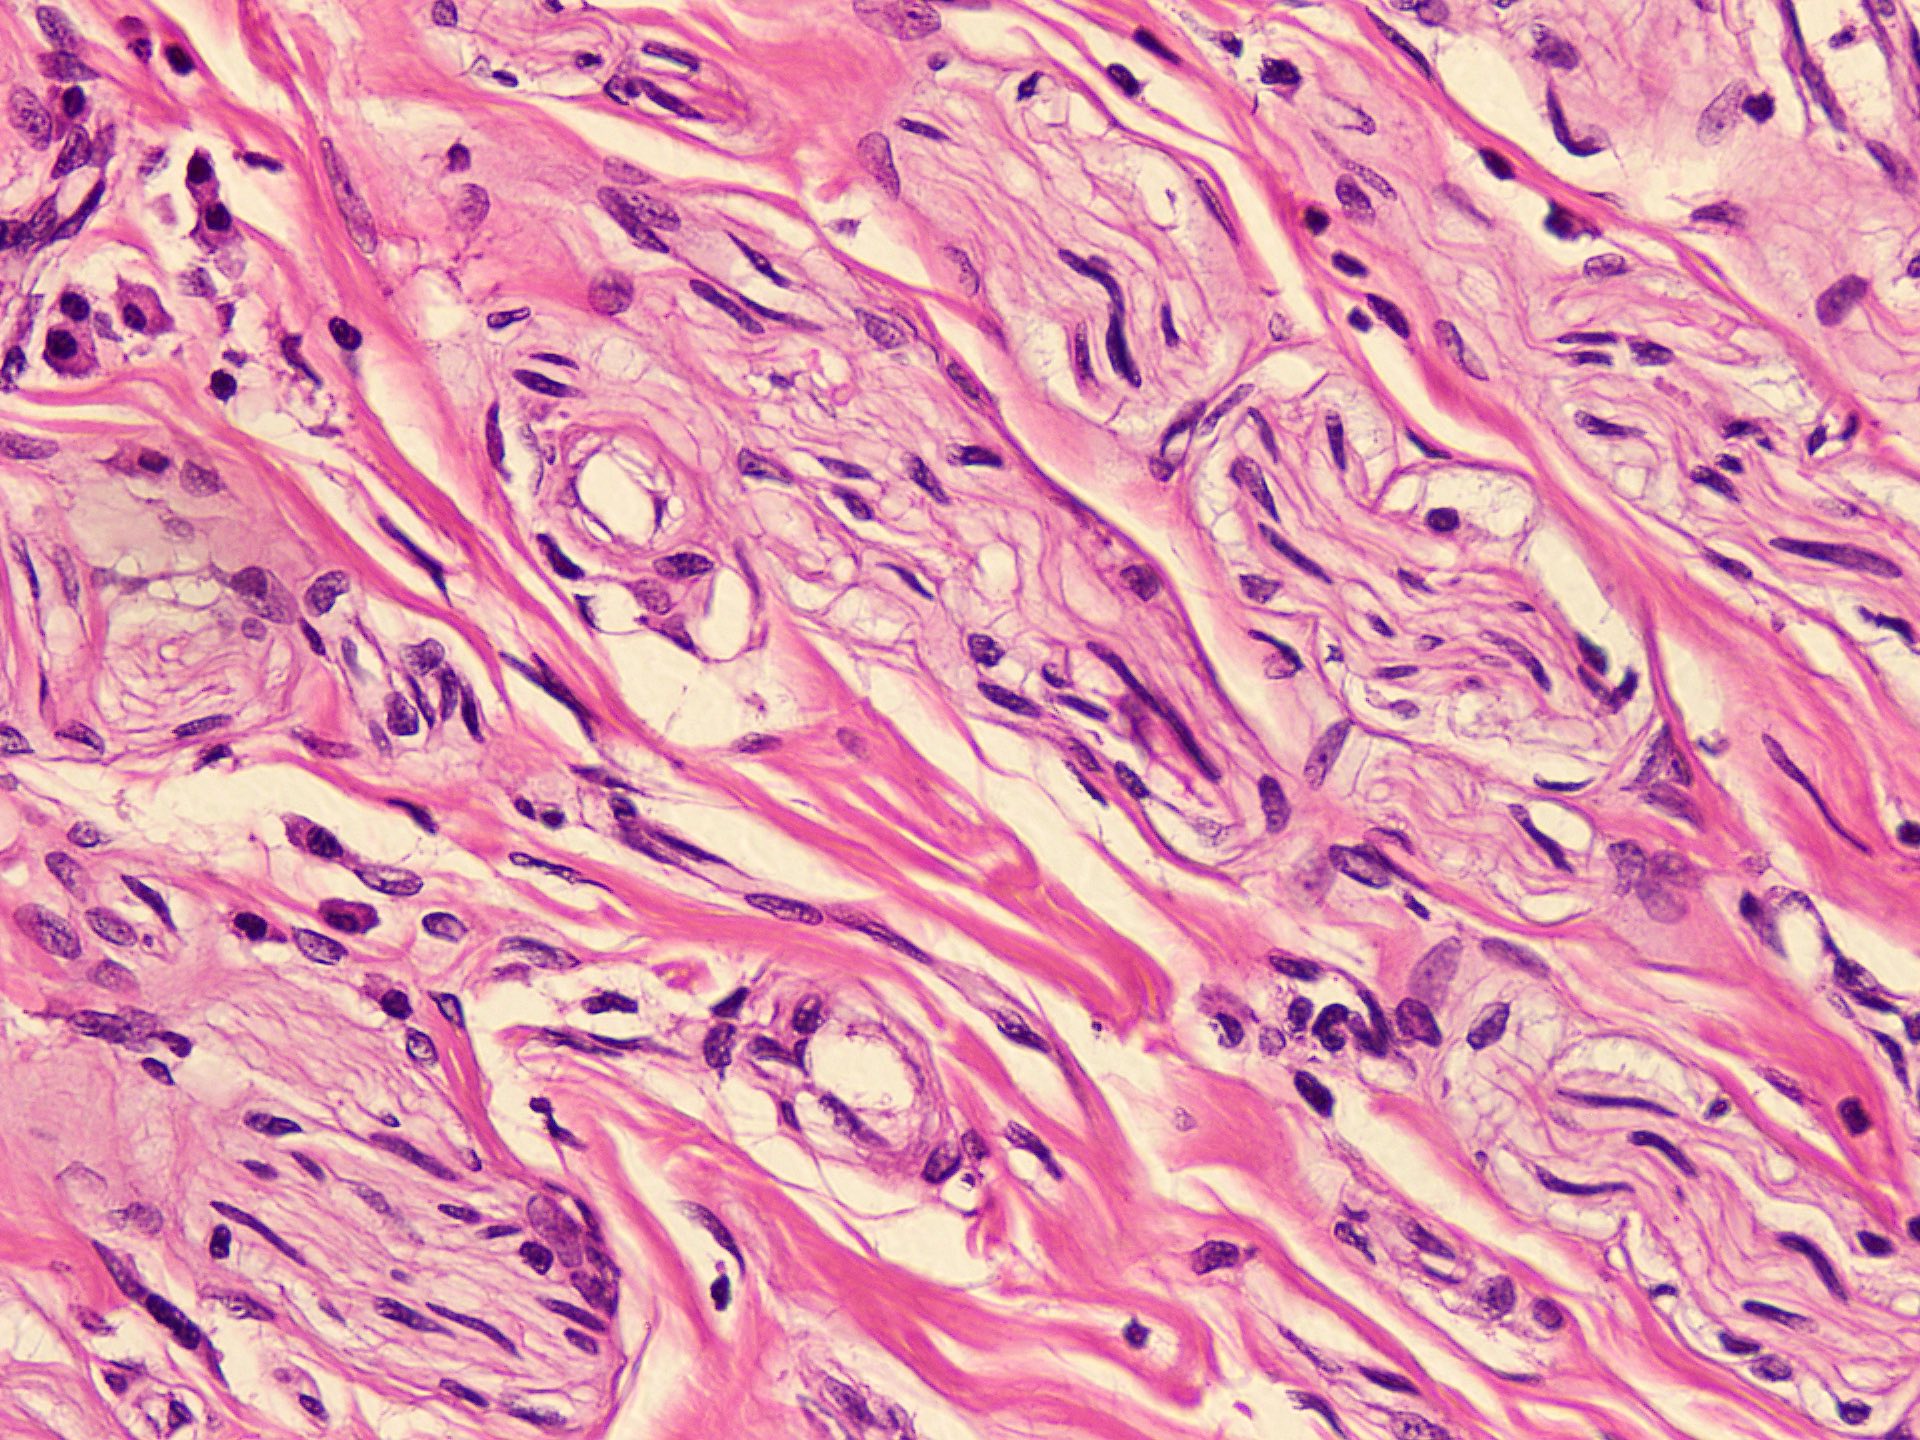

Microscopic (histologic) description

- Circumscribed, unencapsulated spindle cell proliferation arranged in short bundles comprised of axons, Schwann cells, endoneurial cells and perineurial cells (World J Clin Cases 2020;8:3821, Acta Biomed 2020;91:122, StatPearls: Neuroma [Accessed 21 September 2022])

- Peripheral palisading is not present (World J Clin Cases 2020;8:3821)

- Prominent scar tissue with dense collagen may be present (Acta Biomed 2020;91:122, StatPearls: Neuroma [Accessed 21 September 2022])

- Dystrophic calcifications are rarely present (Acta Biomed 2020;91:122)

Microscopic (histologic) images

- Microscopy: The sections examined show a circumscribed, unencapsulated lesion composed of variable sized, closely packed nerve bundle along with scar tissue in the background.

A patient presented with a painful nodule that developed after an amputation of the left first finger. On examination, the nodule is painful. Excision of the lesion is performed which shows the histology above. Which of the following is the most likely diagnosis?